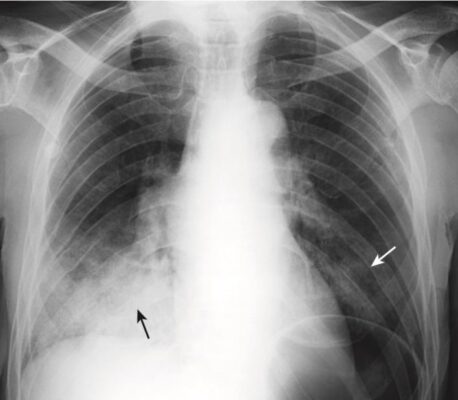

- Hít phải có xu hướng ảnh hưởng đến bất kỳ phần nào của phổi nằm thấp nhất vào thời điểm bệnh nhân hít phải, và các biểu hiện của nó phụ thuộc vào (các) chất được hít vào. Đối với hầu hết các bệnh nhân nằm giường, hít phải thường ảnh hưởng đến các thùy dưới hoặc phần sau của thùy trên.

- Do đặc điểm về đường đi và kích thước của phế quản chính bên phải, hít phải thường xảy ra ở thùy dưới bên phải hơn là thùy dưới bên trái (Hình 7 ).

- Hình ảnh chụp X quang của hít phải và bệnh khỏi nhanh như thế nào tùy thuộc vào loại chất hít phải và có bị nhiễm trùng hay không. Hít phải dịch vị sạch hoặc nước thường sạch nhanh trong vòng 24 đến 48 giờ, trong khi hít phải bội nhiễm có thể mất vài tuần mới khỏi.